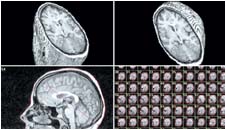

جراحة العيون بالتلسكوبات الفضائية |  في سابقة تعد الأولى من نوعها استخدمت تقنية التليسكوبات الفضائية في مجال جراحة العيون مما أظهر الجانب التشريحي من العين بكل تعقيداته كما لم يظهر من قبل وتعتمد هذه التقنية الطبية الجديدة على ما ........التفاصيل |